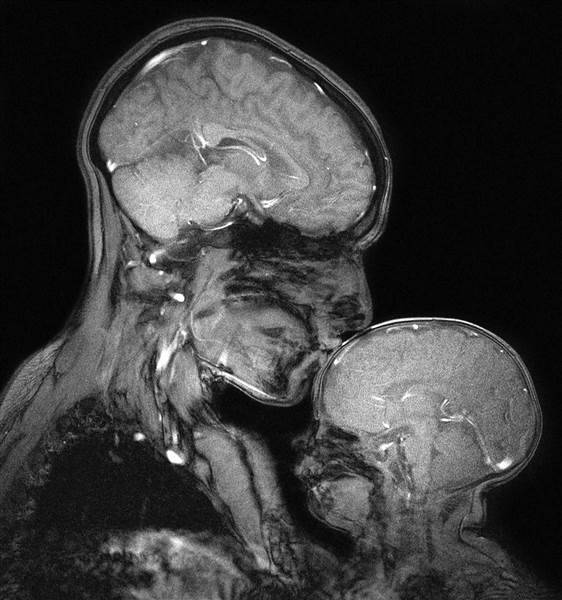

La risonanza magnetica può catturare l’amore: la foto virale di una scienziata

Protagonisti della scansione sono Rebecca Saxe, una neuroscienziata del dipartimento scienze cognitive del MIT e il figlio Percy di 2 mesi. Si potrebbe parlare di una “maternità ultramoderna”. La dottoressa Saxe, assieme al collega Atsushi Takahashi, hanno prodotto l’immagine non per diagnosticare eventuali problemi, ma solo per il gusto di vedere come appariva un bacio di una mamma al figlio.

Affascinante è sicuramente il confronto tra il cervello dell’adulto e il cervello del bambino. “Alcune persone guardano e vedono soprattutto le differenze: come è sottile il cranio, quanto poco spazio ci sia tra il mondo esterno e il suo cervello: solo un piccolo, sottile e fragile guscio“, ha detto Saxe a Today. “D’altra parte, si può guardare e vedere quanto simile sia al cervello di sua madre. Quanto vicino in termini di dimensioni. Molto più vicino in termini di dimensioni che non la sua mano.” La più grande differenza, sottolinea Saxe, è che il cervello di un bambino non ha quasi mielina, la guaina isolante che protegge le cellule nervose del cervello. Saxe, che è un’assistente professore di neuroscienze cognitive presso il MIT, studia come i nostri cervelli costruiscono i pensieri e il linguaggio: si interessa in modo particolare al modo in cui il cervello acquisisce e sviluppa tali capacità durante l’infanzia.

La stessa racconta che dopo aver dato alla luce il primo figlio ha studiato per molto tempo lo sviluppo del suo cervello grazie alla risonanza magnetica: “Nel mio laboratorio, al MIT, usiamo la Risonanza Magnetica per vedere il flusso sanguigno nei cervelli dei bambini; leggiamo loro delle storie e osserviamo come la loro attività cerebrale cambia in reazione alla trama. Così facendo, investighiamo su cosa pensano i bambini dei pensieri altrui” ha scritto Saxe sul Smithsoninamag. “Sentivo come se la mia esperienza di essere sua madre e la mia esperienza di essere un neuroscienziato si fossero improvvisamente e profondamente intrecciate.” È così che ha iniziato a pensare a catturare un’immagine di risonanza magnetica di se stessa con il suo bambino. Poiché però lo scanner non era configurato per catturare immagini di 2 persone, ci sono volute un sacco di modifiche e mesi di trattative con i tecnici per capire come fare. Per 2 giorni lei e Percy hanno passato 2 ore in fase di scansione al fine di ottenere l’immagine che vediamo, che è quella scelta tra 25 tentativi. La difficoltà consisteva nel dover restare immobili per almeno un paio di minuti e riuscire a farlo con un bambino piccolo è quasi impossibile. Inoltre la macchina è molto rumorosa, infatti la mamma ha indossato tappi per le orecchie mentre il bimbo delle cuffie, che hanno funzionato: Percy nella foto dormiva.

Questa mamma conclude il suo racconto dicendo: “La Madre e il Bambino è un potente simbolo di amore e innocenza, bellezza e fertilità. Sebbene tali valori materni, e le donne che li incorporano, possono essere venerati, normalmente sono visti in opposizione ad altri valori: ricerca e intelletto, progresso e potere. Ma io sono una neuroscienziata e ho lavorato per creare quest’immagine; e sono anche una madre in essa, rannicchiata su mio figlio neonato“.